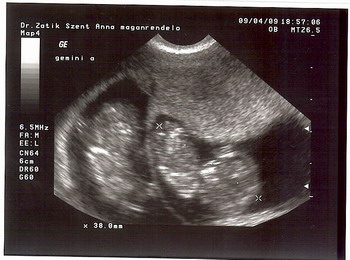

Este UH Dr Zatik Jánosnál (szimpi doki). Mindkét drágánk 38 mm-es, 11 hetes + 1 naposnak felelnek meg, szal szép nagyok. :D És az egyik integetett nekünk meg vizibiciklizett. :) A másik is eleven volt egy pár percig, de aztán megszeppent a "kamerától", és befordult. :lol: